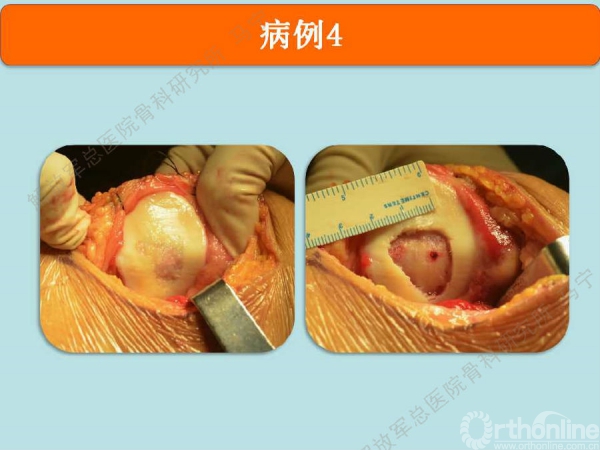

病例-4

姜**:男,33岁 ,双膝疼痛,活动受限1年,曾经打过玻璃酸钠,效果都不理想,来我院行软骨修补术,MRI显示髌骨软骨下骨增生明显,并开始磨损滑车。

术中显示软骨损伤的面积比核磁上的范围要大很多。

上图是我们院自主研发的以软骨细胞外基质为原料的孔隙取向性支架。可以做成任意厚度任意大小,按照软骨缺损的形状裁剪好以后。这个损伤面积大概在4平方厘米左右。